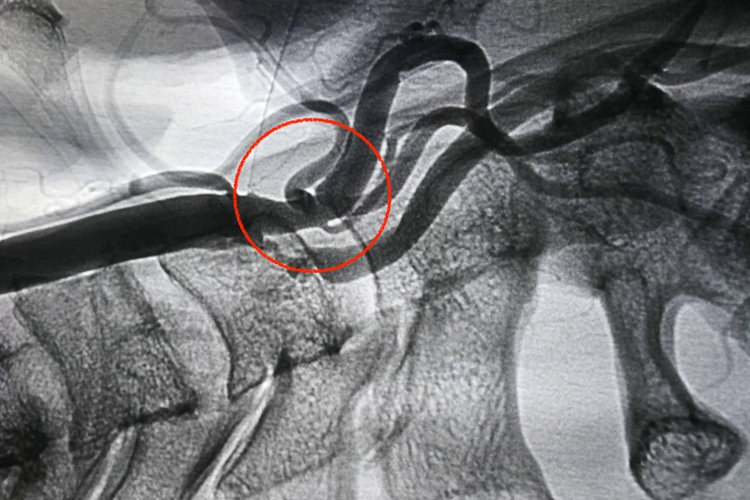

手术治疗:必要时患者可以在医生指导下根据血管狭窄的程度、斑块的稳定性,结合患者的症状、基本情况进行手术治疗,手术方式包括动脉内膜剥脱术和动脉支架植入术等。